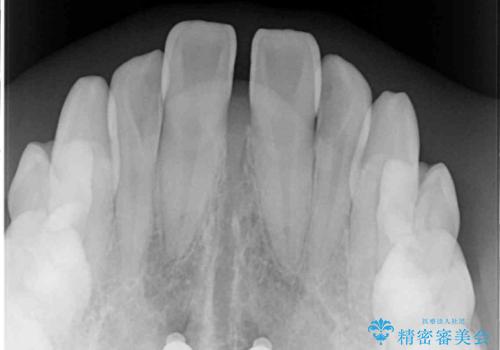

- 奥歯の反対咬合を気にして来院された患者様です。

反対咬合は上顎骨の幅が下顎骨よりも小さいことが原因なので、拡大装置により骨幅を広げて上下関係を改善し、その後インビザラインにて歯並びを整えることとしました。

反対咬合が改善され、食いしばり癖もなくなり、顎関節の負担が軽減されました。

上顎骨を拡大したことで前歯に隙間ができ、1ヶ月ほど恥ずかしい時期がありましたが、しっかりとした咬み合わせに仕上がり、患者様には大変満足していただきました。